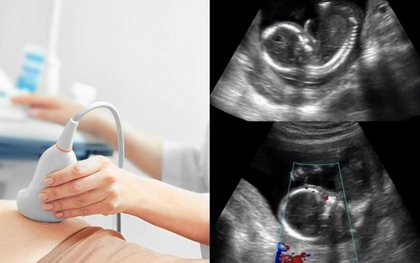

Đến tối cùng ngày, chị nhận thấy thai nhi không còn cử động. Ngay lập tức, gia đình đưa chị đến phòng khám gần nhất, nhưng mọi nỗ lực đều không thể cứu vãn.

Vừa qua (ngày 29/3) Sở Y tế Hà Nội đã ra văn bản đình chỉ lưu hành thuốc viên nén Misoprostol không đạt tiêu chuẩn chất lượng gửi đến các đơn vị y tế trực thuộc ngành, phòng y tế quận, huyện, thị xã.